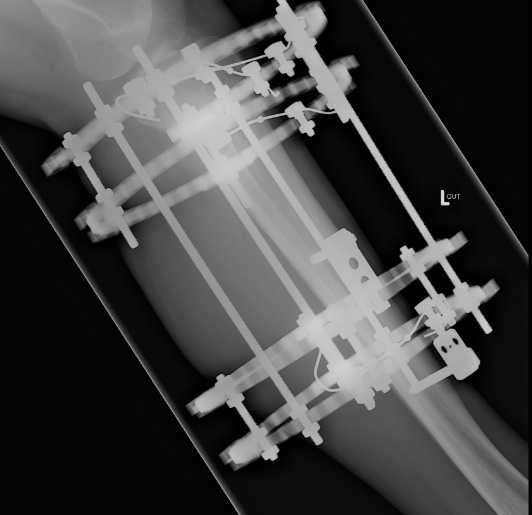

Ilizarov Frame

- controls torsion and shear well

- allows axial compression and controlled micromotion

- this improves bone healing compared to standard external fixation

- tensioned wires tend to loosen over time and improve this situation with further loading

Can compress / lengthen

- lengthen and shorten struts

- allows compression of non union

- allows distraction osteogenesis of corticotomies

Components

1. High tension wires

- straight or olive

- 90 - 130 kg

- 90o to each other

Olive wires

- used to aid indirect reduction

Tension

- fix one end, tighten the other

Offset wires from rings

- using posts

2. Pins

Use in conjunction to wires

- never at same level as each other to avoid stress riser

- 4, 5 or 6 mm

- connected to ring via rancho cubes with centering sleeves

At least 2 planes of wires / half pins in each major bone segment

- very normal to use 1 tensioned wire and two HA coated half pins

- if have 3-4 wires / half pins can remove 1 (i.e. from loosening or infection) without loosing stability of construct

3. Rings

Various sizes

- always need extra room posteriorly

- 2-3cm space to skin circumferentially

- proximal ring open posteriorly to allow flexion

- always 2 level fixation in each level for control

- can be one ring, but wires & half pins above and below